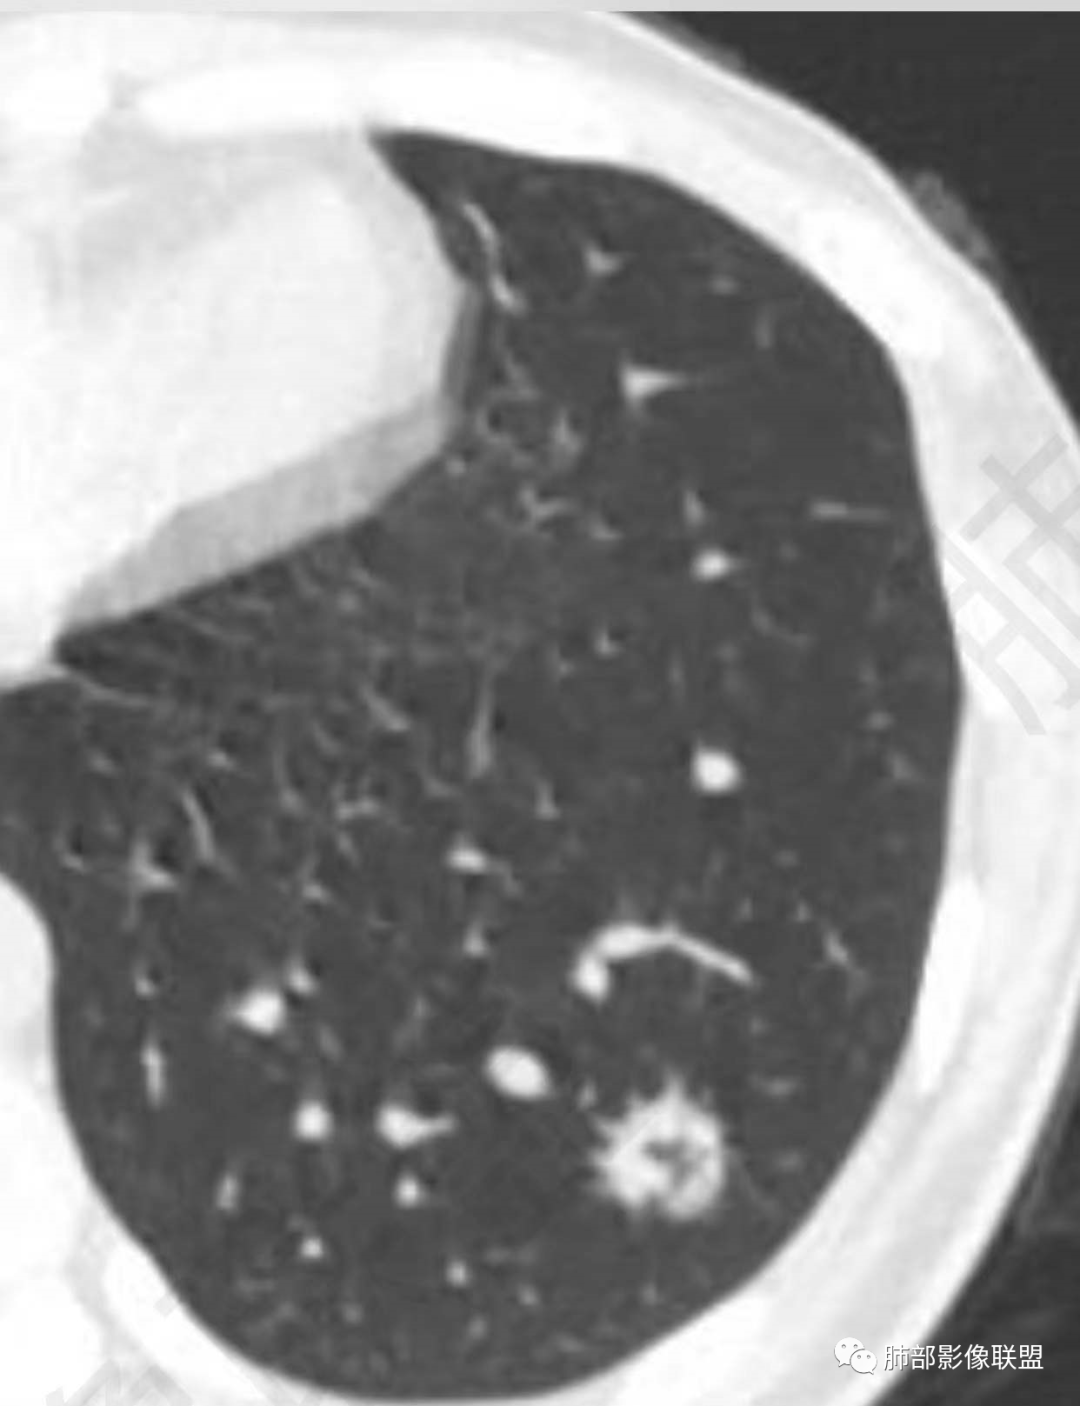

2、影像特点:左肺下叶类圆形结节影,周围可见多发细小毛刺,浅分叶,张力不高,未见胸膜牵拉。病灶内隐约见空泡影(未提供CT值),近端部分血管呈杵状增粗,可疑脐凹征。增强后实性部分有轻度强化。外围病灶,与支气管关系不明确。

左下肺结节,局部边缘见u型凹陷及平直征,可见长毛刺,周围肺野可见斑点状播散灶,结节内可见低密度坏死,坏死边界清,坏死壁上可见结节堆彻,低强化,延迟强化呈环状,年轻患者,肿标阴性,综合分析首选炎性肉芽肿性病变,TB可能性大,其次鉴别腺癌

年轻女性,体检发现,左肺下叶亚实性结节,边缘有毛刺、分叶,磨玻璃晕,病灶内可见裂隙样空腔改变,纵隔窗显示实性小于肺窗,近端血管呈杵状增粗,考虑腺癌,鉴别炎性结节(隐球菌),转移性结节。